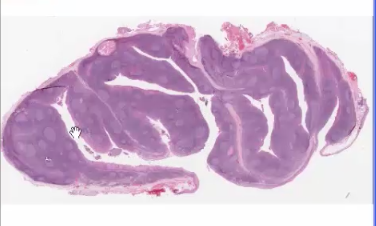

How to differentiate between tonsils and other structures of the immune system

Tonsils have characteristic crypts

How can we differentiate between pharyngeal tonsil and palantine tonsil

Palantine has stratified squamous epithelium whereas the pharyngeal has ciliated pseudostratified columnar epithelium